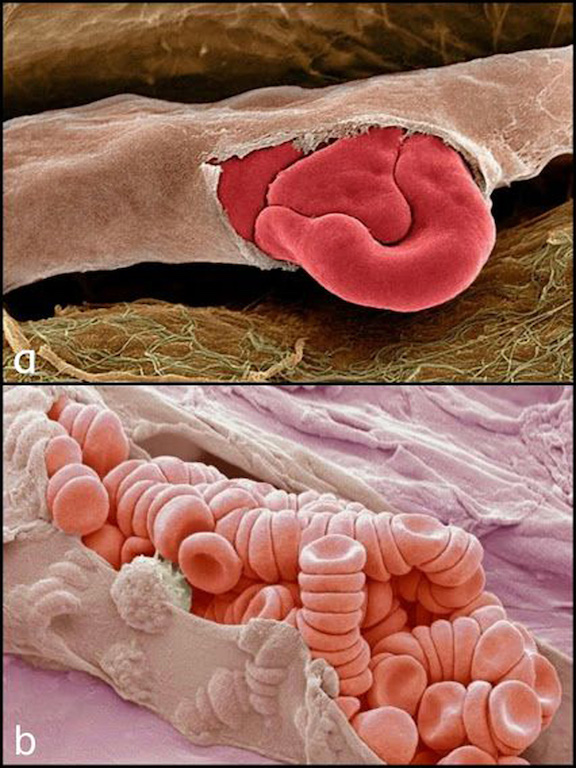

Primer punto, el alto grado de detalle que tienen las fotos. Se nos dificulta concebir un ojo, un óvulo, un pulmón, el iris del ojo, la célula capilar del oído, como unidades separadas y no como partes de un todo.

Ahora, comencemos el recorrido. Disfrutemos de estas imágenes, permitiéndonos experimentar la fascinación, la impresión o la repulsión, sabiendo que, mirado tan de cerca, nuestro cuerpo puede resultarnos más parecido a una obra de arte abstracto que a la experiencia de tener un cuerpo.